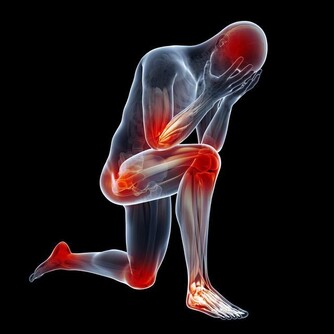

痛風病發生在任何年齡,但最常見的是40歲以上的中年男人,

並且發病人群有越來越年輕化的趨勢,這是為什麼呢?

1、 年齡因素:年齡大的人比年輕的人易患痛風,發病年齡約為45歲左右。

不過,由於近年來人們生活水平普遍提高,營養過剩,運動減少,痛風正在向低齡化發展。

現在30歲左右的痛風患者也很常見。

2、 體重因素:肥胖的中年男性易患痛風,尤其是不愛運動、進食肉類蛋白質較多、營養過剩的人比營養一般的人易患痛風。

3、 性別因素:男人比女人易患痛風,男女發病比例為20:1。而且,女性患痛風幾乎都是在絕經以後,這可能與卵巢功能的變化及性激素分泌的改變有一定的關係。

4、 職業因素:企事業幹部、教師、私營企業主等社會應酬較多和腦力勞動者易患痛風。

5、 飲食因素:進食高嘌呤飲食過多的人易患痛風,貪食肉類的人比素食的人易患痛風。

6、 遺傳因素也是一方面,痛風是一種遺傳代謝性疾病,具有遺傳性。患有痛風病的家族裡,如果不調節自己的飲食習慣,就很容易患上痛風。因為體內缺少一種酶,就不能把蛋白質分解。最後結晶成小晶體堆積在關節內,誘發疾病。